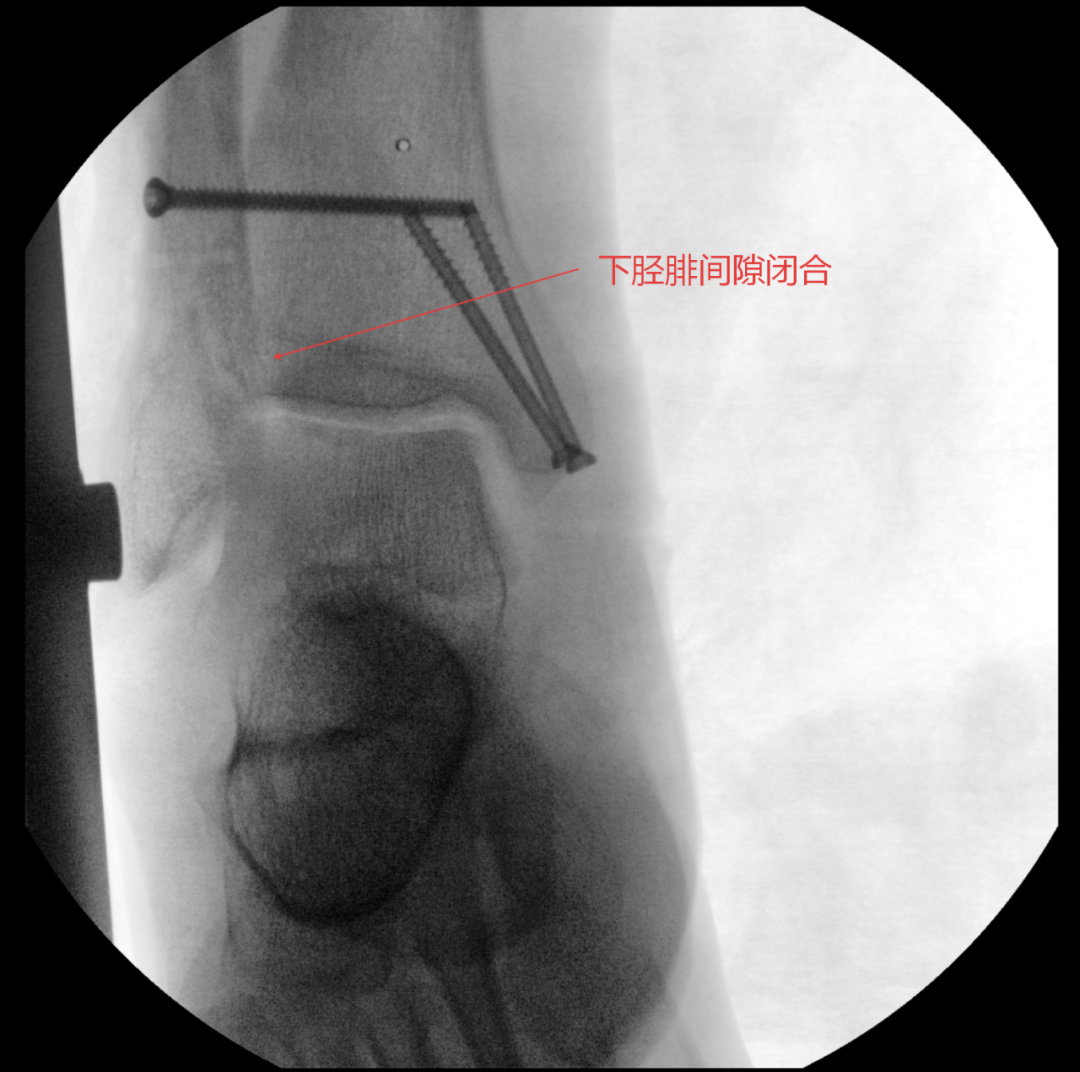

术中进行下胫腓拉力试验结果呈明显阳性,且复位效果未达预期,团队当机立断决定切开探查,发现前结节骨折块嵌顿于下胫腓间隙,正是阻碍复位的关键,取出骨折块后顺利完成复位,手术按规范流程顺利结束。